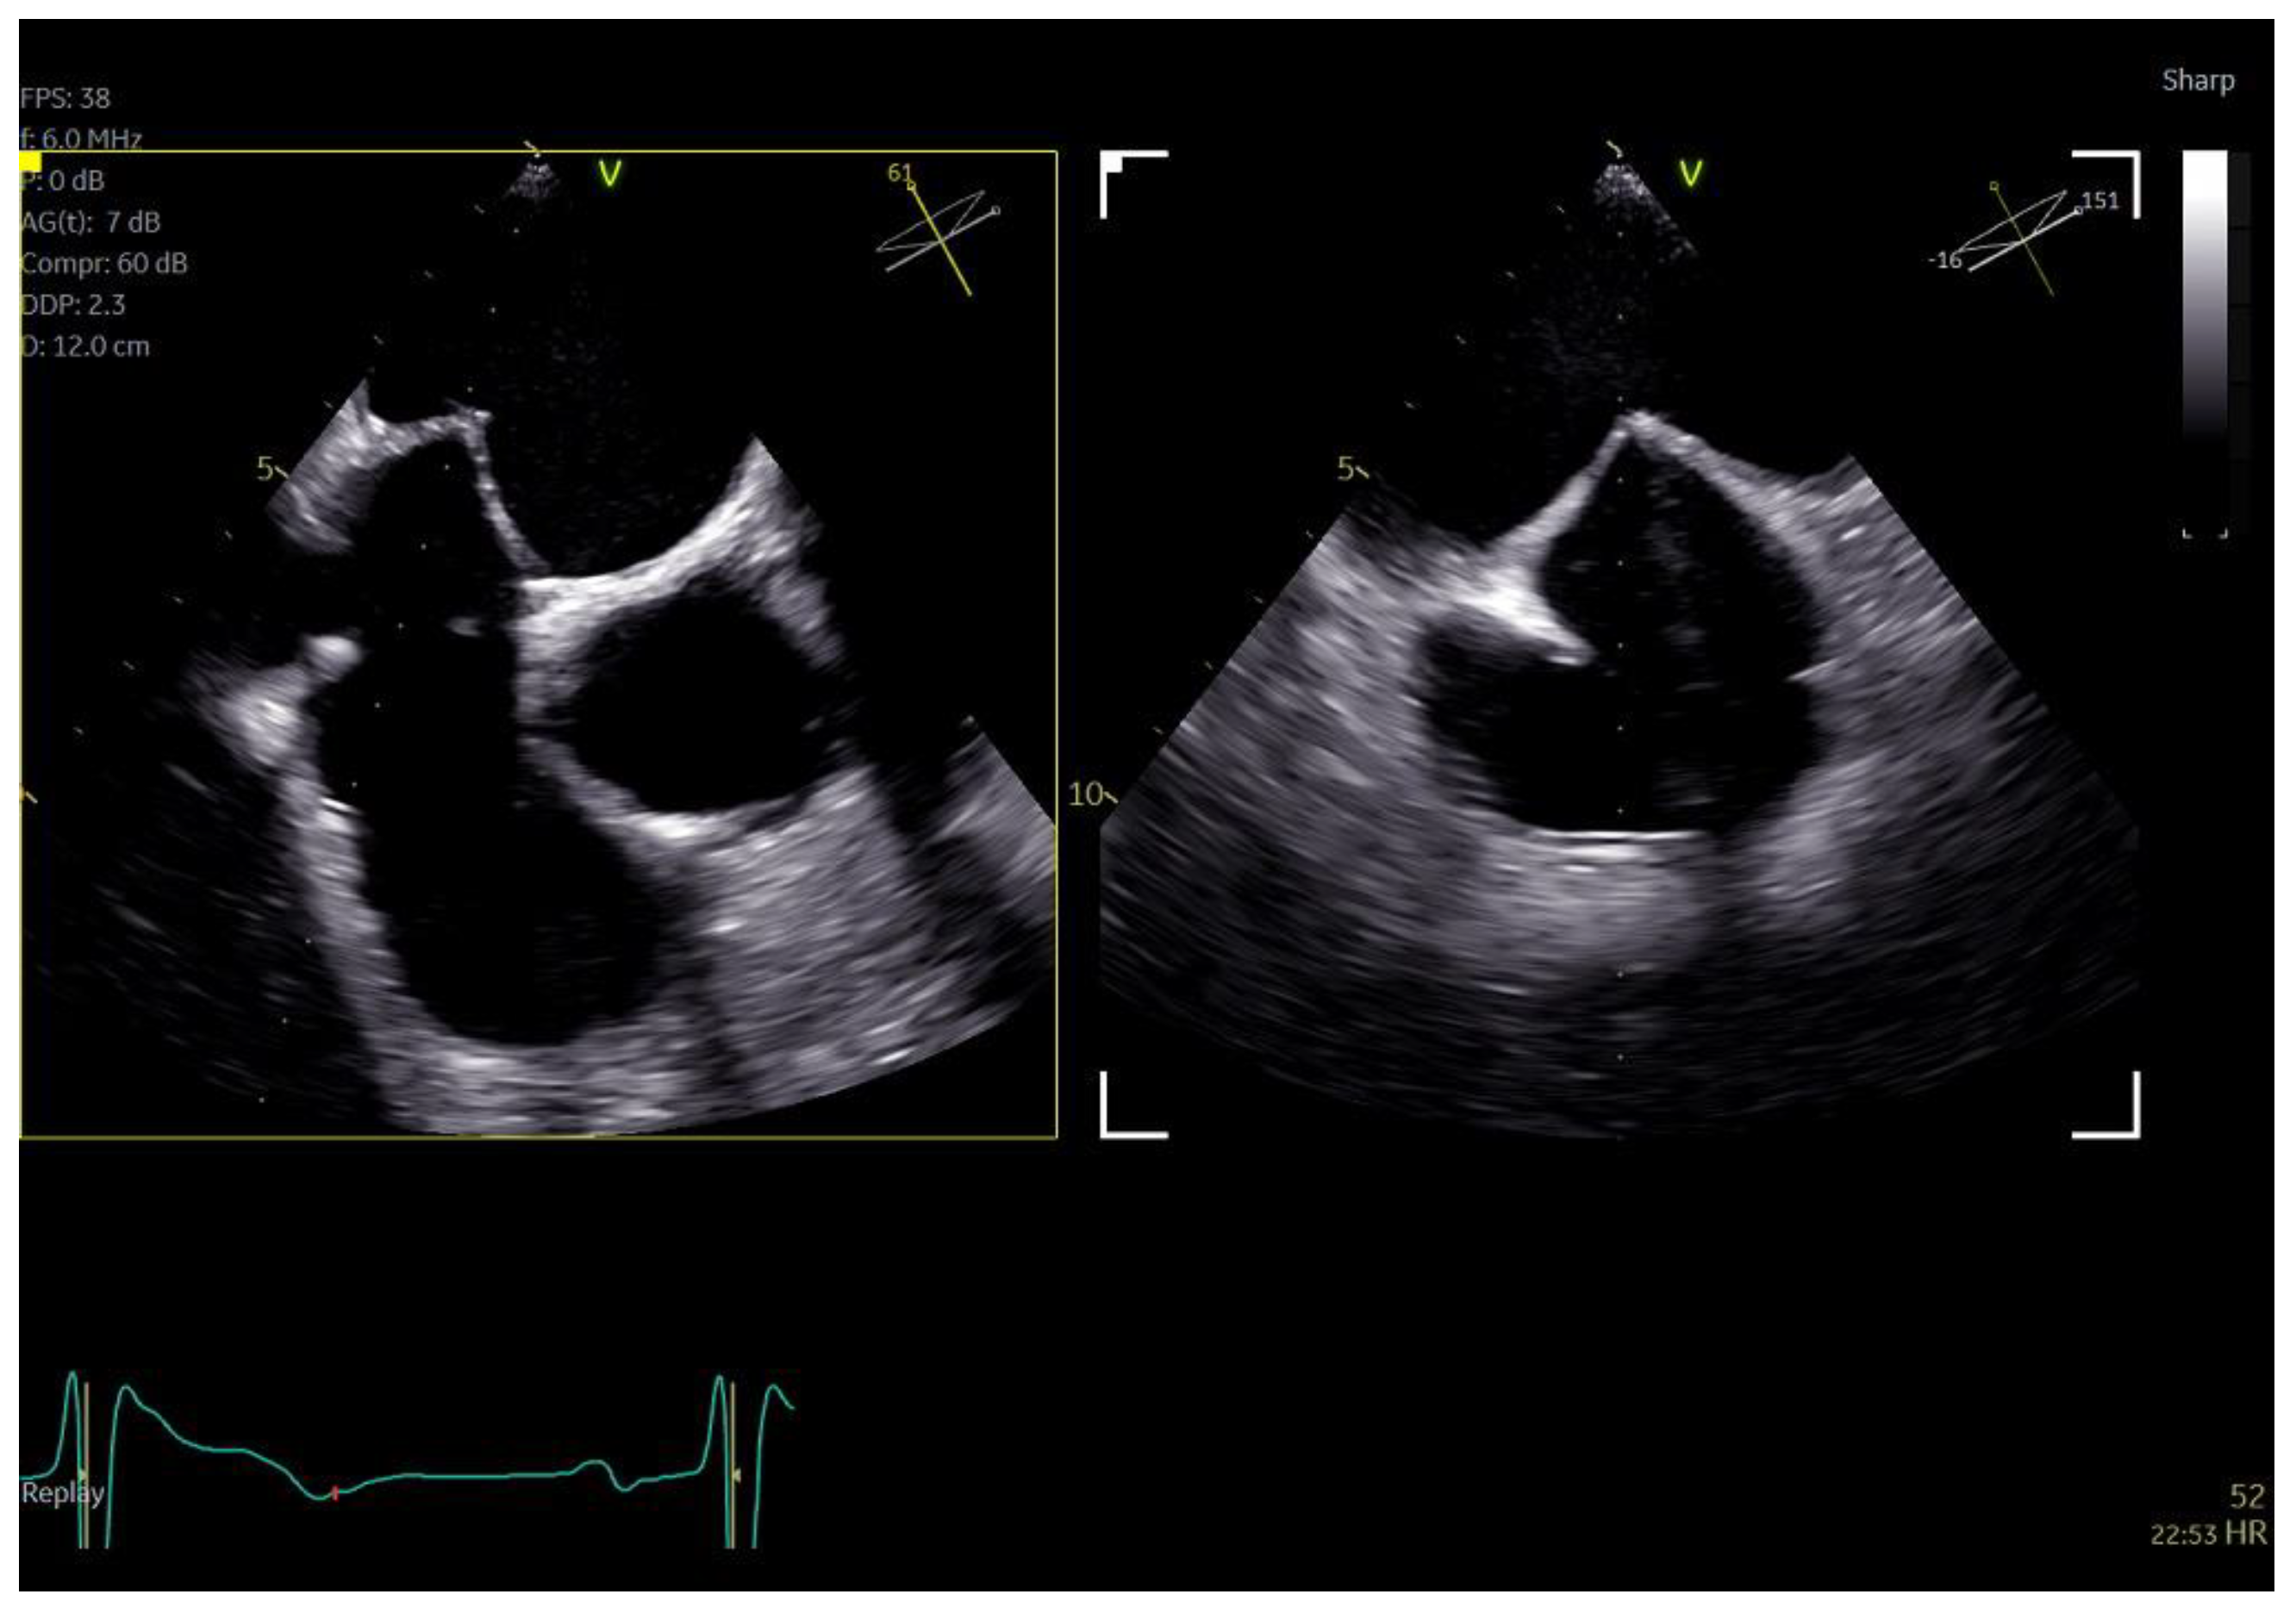

Regarding imaging quality, almost all patients exhibited excellent images without any compromise in resolution, obviating the need to confirm findings using the standard TEE probe (Figure 3 and Figure 4, video S5). Despite the one patient requiring additional sedation due to intense pharyngeal reflex, the quality of images obtained remained consistent across all cases. In 22 cases out of 30 included in this study, the 2D and 3D imaging quality received a score of 5 suggesting excellent imaging totally equal to the one acquired with the adult probe. In four cases, 2D and 3D images were commented as good with a score of 4 and in another four cases, while the 2D images were excellent, 3D images were again mentioned to be good, almost equal to the standard probe but not exceptional enough to receive a grade of 5 (Table 3).

Figure 3.

Dual crop 3D volume-rendered atrial (left) and ventricular (right) views of normal mitral valve.